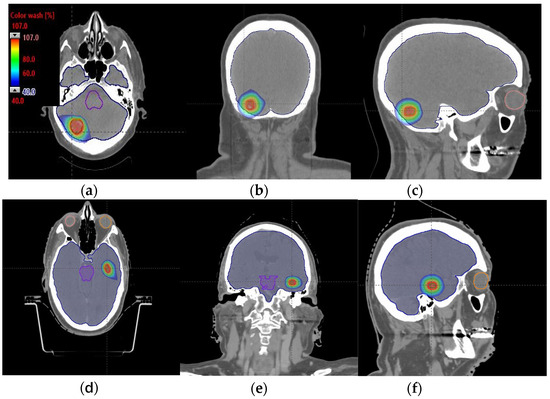

Figure 8.

Axial, coronal, and sagittal CT slices of head and neck cancer patients 1 (a–c) and 2 (d–f). Dose distribution is displayed showing isodose curves in a range from 40% (blue) to 107% (red) of the prescribed dose.

An MIBE of 160 MeV is the appropriate value to consider based on the results obtained for tumor coverage and homogeneity and dose sparing in healthy tissue (Table 3). The color coding is the same as that in Table 1. Figure 7a–d display the DVHs of the created proton treatment plans. We have also included slices (axial, sagittal, and coronal views) with the dose distribution overlayed (Figure 8a–f). For the two patients assessed, the developed plans displayed in Figure 8a–f correspond to a 160 MeV MIBE proton plan.